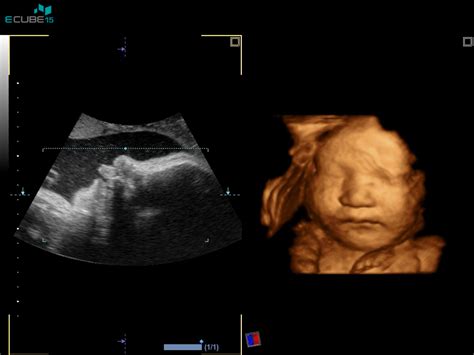

V 13. tednu nosečnosti je vaš bodoči dojenček že precej bolj razvit in se začne bolj približevati človeški obliki. Velikost ploda v 13. tednu je primerljiva z velikostjo limone, saj v povprečju meri okoli 7,4 cm in tehta približno 23 gramov. Nekateri viri navajajo, da v tem času meri med 70-75 mm in tehta približno 25 miligramov. Čeprav je še majhen, se v njem dogajajo pomembne spremembe.

V tem tednu na drobnih prstkih vašega ploda pričnejo nastajati prstni odtisi. Žile in organi ploda so jasno vidni skozi zelo tanko kožo, telo pa v rasti počasi pričenja dohitevati glavo. Če je plod deklica, ima zdaj v jajčnikih več kot 2 milijona jajčec. V telesu vašega otroka začenjajo delovati jetra in trebušna slinavka. Odvisno od spola, se zdaj v celoti oblikujejo jajčniki oziroma testisi, razvijati pa se začnejo tudi zunanja spolovila. Kljub temu, da se spol že razvija, ultrazvok v 13. tednu še ni dovolj zanesljiv za določitev spola, zato zdravnik najverjetneje ne bo želel “ugibati”. Točnejšo informacijo bo morda dal na pregledu v 20. tednu med morfologijo.

Pri pregledu v 13. tednu nosečnosti bo ginekolog pozorno pregledal velikost različnih delov otroka. Pomemben del njegovega razvoja, ki ga je zdaj že moč izmeriti, je tako imenovana nuhalna svetlina, nabrana tekočina v podkožju plodovega zatilja. V prihodnjih tednih bo popolnoma izginila. Količina tekočine kaže na to, ali ima vaš otrok različne težave, na primer srčno napako ali Downov sindrom.